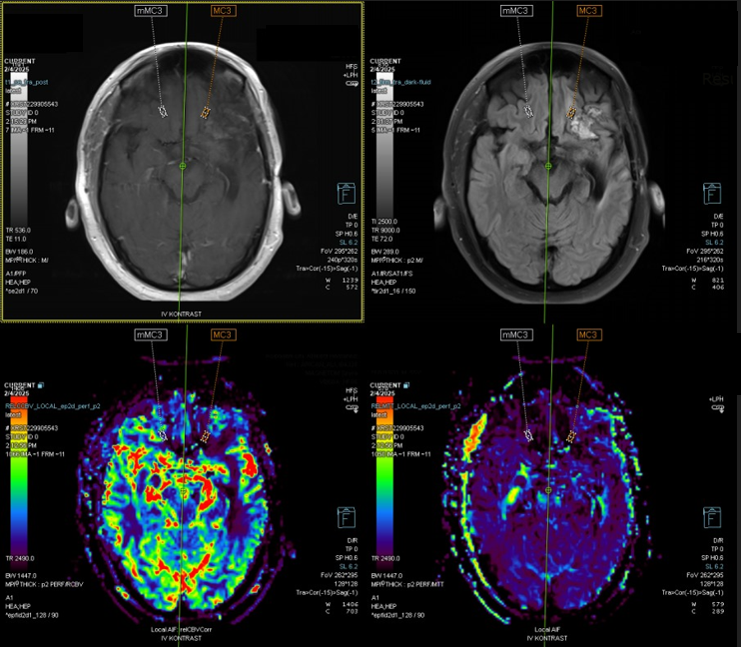

Perfusion MRI is an advanced imaging technique that measures cerebral blood flow (CBF), providing critical information about the blood supply to brain tissues. It evaluates the circulation dynamics, especially the flow of oxygenated blood through the cerebral vasculature, and identifies areas with compromised perfusion.

• Brain Tumors: Perfusion MRI is valuable in assessing tumor vascularity, particularly in malignant tumors like glioblastomas, which exhibit high blood flow. This helps distinguish aggressive tumors from benign lesions and aids in surgical planning.

• Tumor Recurrence vs. Radiation Necrosis: One of the key applications of Perfusion MRI in the postoperative period is differentiating tumor recurrence from radiation necrosis following radiotherapy. Tumor recurrence typically presents with increased perfusion due to the angiogenesis (new blood vessel formation) associated with tumor growth. In contrast, radiation necrosis often shows low perfusion due to damaged blood vessels. Perfusion MRI can help distinguish these two conditions, guiding clinical decision-making and further treatment interventions.